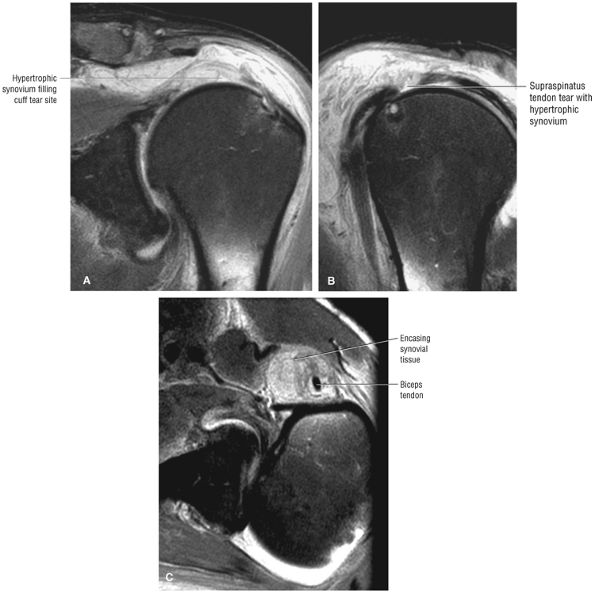

FIGURE 8.102 ● (A) The anterior undersurface of the acromion and the coracoacromial ligament form the coracoacromial arch. The subacromial subdeltoid bursa facilitates the passage of the rotator cuff and proximal humerus under the coracoacromial arch. (B) A superior axial image shows the anterior-to-posterior extent of the coracoacromial (CA) ligament perpendicular to the supraspinatus tendon. The fluid in the subacromial-subdeltoid bursa represents fluid between two serosal surfaces in contact with each other. One serosal surface is contributed by the undersurface of the coracoacromial arch and deltoid, and the other serosal surface is on the bursal side of the cuff.

|

![]() |

FIGURE 8.103 ● Pseudospur. The normal broad attachment of the coracoacromial ligament to the inferior surface of the acromion is shown on (A) T1-weighted coronal oblique and (B) sagittal oblique images. The low-signal-intensity acromial cortex (black arrows) and adjacent coracoacromial ligament and lateral slip of the deltoid attachment (white arrows) give the false impression of a small subacromial spur in the coronal plane. This pseudospur should not be misinterpreted as impingement; otherwise, unnecessary acromioplasties may be performed on patients with a normal coracoacromial ligament attachment and no associated acromial spurs.